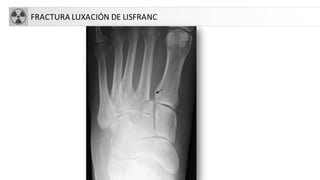

• Fractura-luxación de Lisfranc:

• Se localiza entre las 3 cuñas y el cuboides y los 5 metatarsianos

• No siempre es fácil el Dx radiológico

• Fracturas de los metatarsianos

• Más frecuente 5º meta

FRACTURASDEL PIE • Fractura-luxaciónde Lisfranc: • Se localiza entre las 3 cuñas y el cuboides y los 5 metatarsianos • No siempre es fácil el Dx radiológico • Fracturas de los metatarsianos • Más frecuente 5º meta